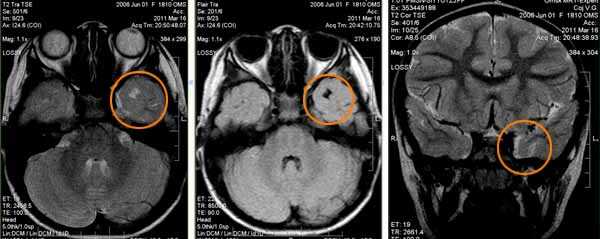

Туберозный склероз. Гамартомы. КТ, Т2-зависимая МРТ и FLAIR

Туберозный склероз. Субэпендимальные узлы. Аксиальная Т-зависимая МРТ.

5. МР-картина узловой субкортикальной гетеротопии левой лобно-теменной области.

В первом случае визуализируются узлы гетеротопии в субкортикальных отделах белого вещества парасагиттальных отделов левой лобно-теменной области.

На втором скане - единичный мелкий узел гетеротопии в белом веществе правой лобной доли (характеристики МР-сигнала идентичны серому веществу головного мозга)

На третьем изображении - множественные узлы гетеротопии вдоль стенок переднего рога левого бокового желудочка и задних рогов обоих желудочков (характеристики МР-сигнала узлов идентичны серому веществу головного мозга)